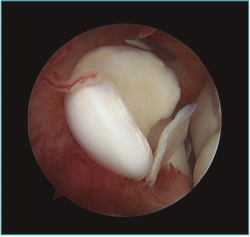

Los portales más adecuados son el anteromedial proximal para la óptica y el anterolateral, el anterolateral proximal y el mediolateral directo o soft-spot (Figura 4) como portales de trabajo. Los portales anteromediales permiten una excelente visualización de la cámara anterior, de la superficie articular de la cabeza radial, del cóndilo humeral, de la apófisis coronoides y de la cápsula anterior y lateral (Figura 5). A este nivel suelen observarse la gran mayoría de los cuerpos libres articulares que en ocasiones se encuentran en la zona lateral y posterior del codo (Figura 6).

Figura 6. Abundante sinovitis y cuerpo libre alojado en cámara anterior en un paciente con lesión osteocondral de tipo IV de la International Cartilage Repair Society (ICRS).